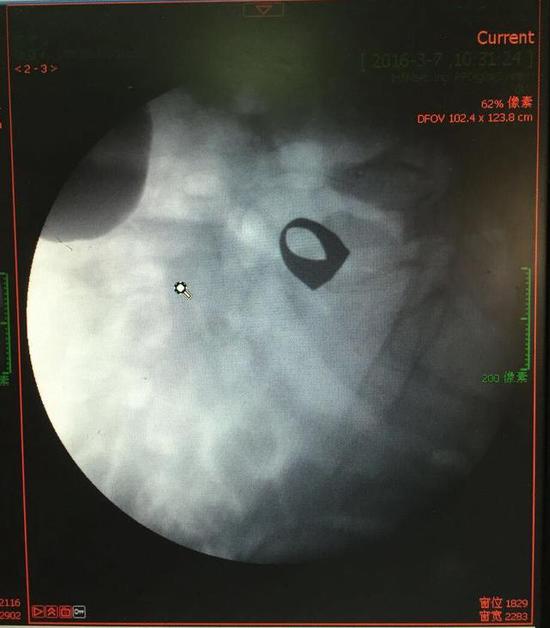

考慮到患者年齡較大,有冠心病,曾經(jīng)中過(guò)風(fēng),高血壓極高危級(jí),遂把老人安排在帶有監(jiān)護(hù)的病房,立即給予吸氧,補(bǔ)液等治療。醫(yī)院立刻開(kāi)啟綠色通道,醫(yī)護(hù)人員專(zhuān)門(mén)陪伴病人做了增強(qiáng)CT,腹部平片,和碘水造影,確定戒指的位置。檢查結(jié)果提示戒指位于右下腹小腸內(nèi),距回盲瓣體表投影約5cm。

此時(shí)一個(gè)又一個(gè)大大的疑問(wèn)出現(xiàn)在每個(gè)在場(chǎng)的醫(yī)護(hù)人員腦海中,戒指還在小腸里嗎?戒指在哪個(gè)位置呢?夏教授立刻聯(lián)系放射科,拍片子,發(fā)現(xiàn)戒指已經(jīng)移動(dòng)了,從右側(cè)移動(dòng)到了左側(cè)去了。放射科醫(yī)師建議,戒指有可能會(huì)繼續(xù)沿腸道下行,如果過(guò)了回盲瓣,就可以自行排出,免除手術(shù)痛苦。教授們采納了這個(gè)意見(jiàn),立即給予促進(jìn)胃腸道動(dòng)力藥,枸櫞酸莫沙必利片,每日口服三次,另外配合灌腸治療,促進(jìn)腸道蠕動(dòng),利于戒指排出。